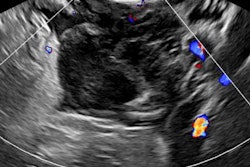

Unlike external ultrasound exams, pelvic ultrasound poses more of a challenge to both learners and educators, the firm said. Simbionix provides a true-to-life training environment and was developed based on American Institute of Ultrasound in Medicine (AIUM) standards and guidelines for the accreditation of ultrasound practices.

Training is performed on a mannequin combined with simulated anatomies and pathologies, 3D Systems said. Virtual patient cases include normal anatomical variations, ectopic pregnancy, fibroids, ovarian malignancies, and hydrosalpynx. Simbionix incorporates didactics, real-time guidance, and captured metrics for objective assessment.